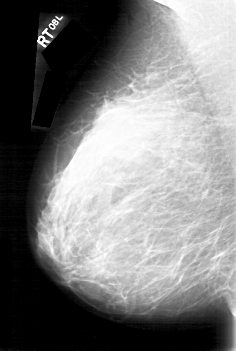

D_4092_1.RIGHT_MLO

RIGHT_CC LINES 5341 PIXELS_PER_LINE 3466 BITS_PER_PIXEL 12 RESOLUTION 43.5 NON_OVERLAY

RIGHT_MLO LINES 5251 PIXELS_PER_LINE 3526 BITS_PER_PIXEL 12 RESOLUTION 43.5 NON_OVERLAY